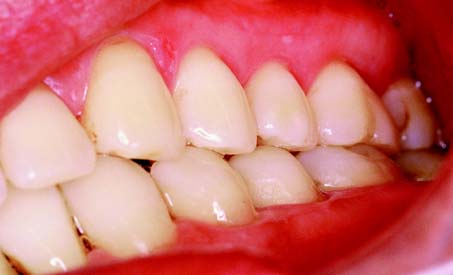

However, in many patients, maximal intercuspal contact occurs with the condyles in a slightly translated position. This position is referred to as maximum intercuspation which is defined as the complete intercuspation of the opposing teeth independent of condylar position, sometimes referred to as the best fit of the teeth regardless of the condylar position. If the mesiobuccal cusp of the maxillary first molar is aligned with the buccal groove of the mandibular first molar, an Angle Class I orthodontic relationship (Fig. 4-4) exists; this is considered normal (see glossary). In such a relationship, the anterior teeth overlap both horizontally and vertically. This position is defined as the dental relationship in which there is normal anteroposterior relationship of the jaws, as indicated by correct intercuspation of maxillary and mandibular molars, but, when a malocclusion is present, there are crowding and rotation of teeth elsewhere (i.e., a dental dysplasia or arch length deficiency). Orthodontic textbooks3 have traditionally described an arbitrary 2 mm for horizontal overlap and vertical overlap as being ideal. For most patients, however, greater vertical overlap of the anterior teeth is desirable, to prevent undesirable posterior tooth contact as a result of flexing of the mandible during mastication. Empirically, dentitions with greater vertical overlap of the anterior teeth appear to have a better long-term prognosis than do dentitions with minimal vertical overlap.